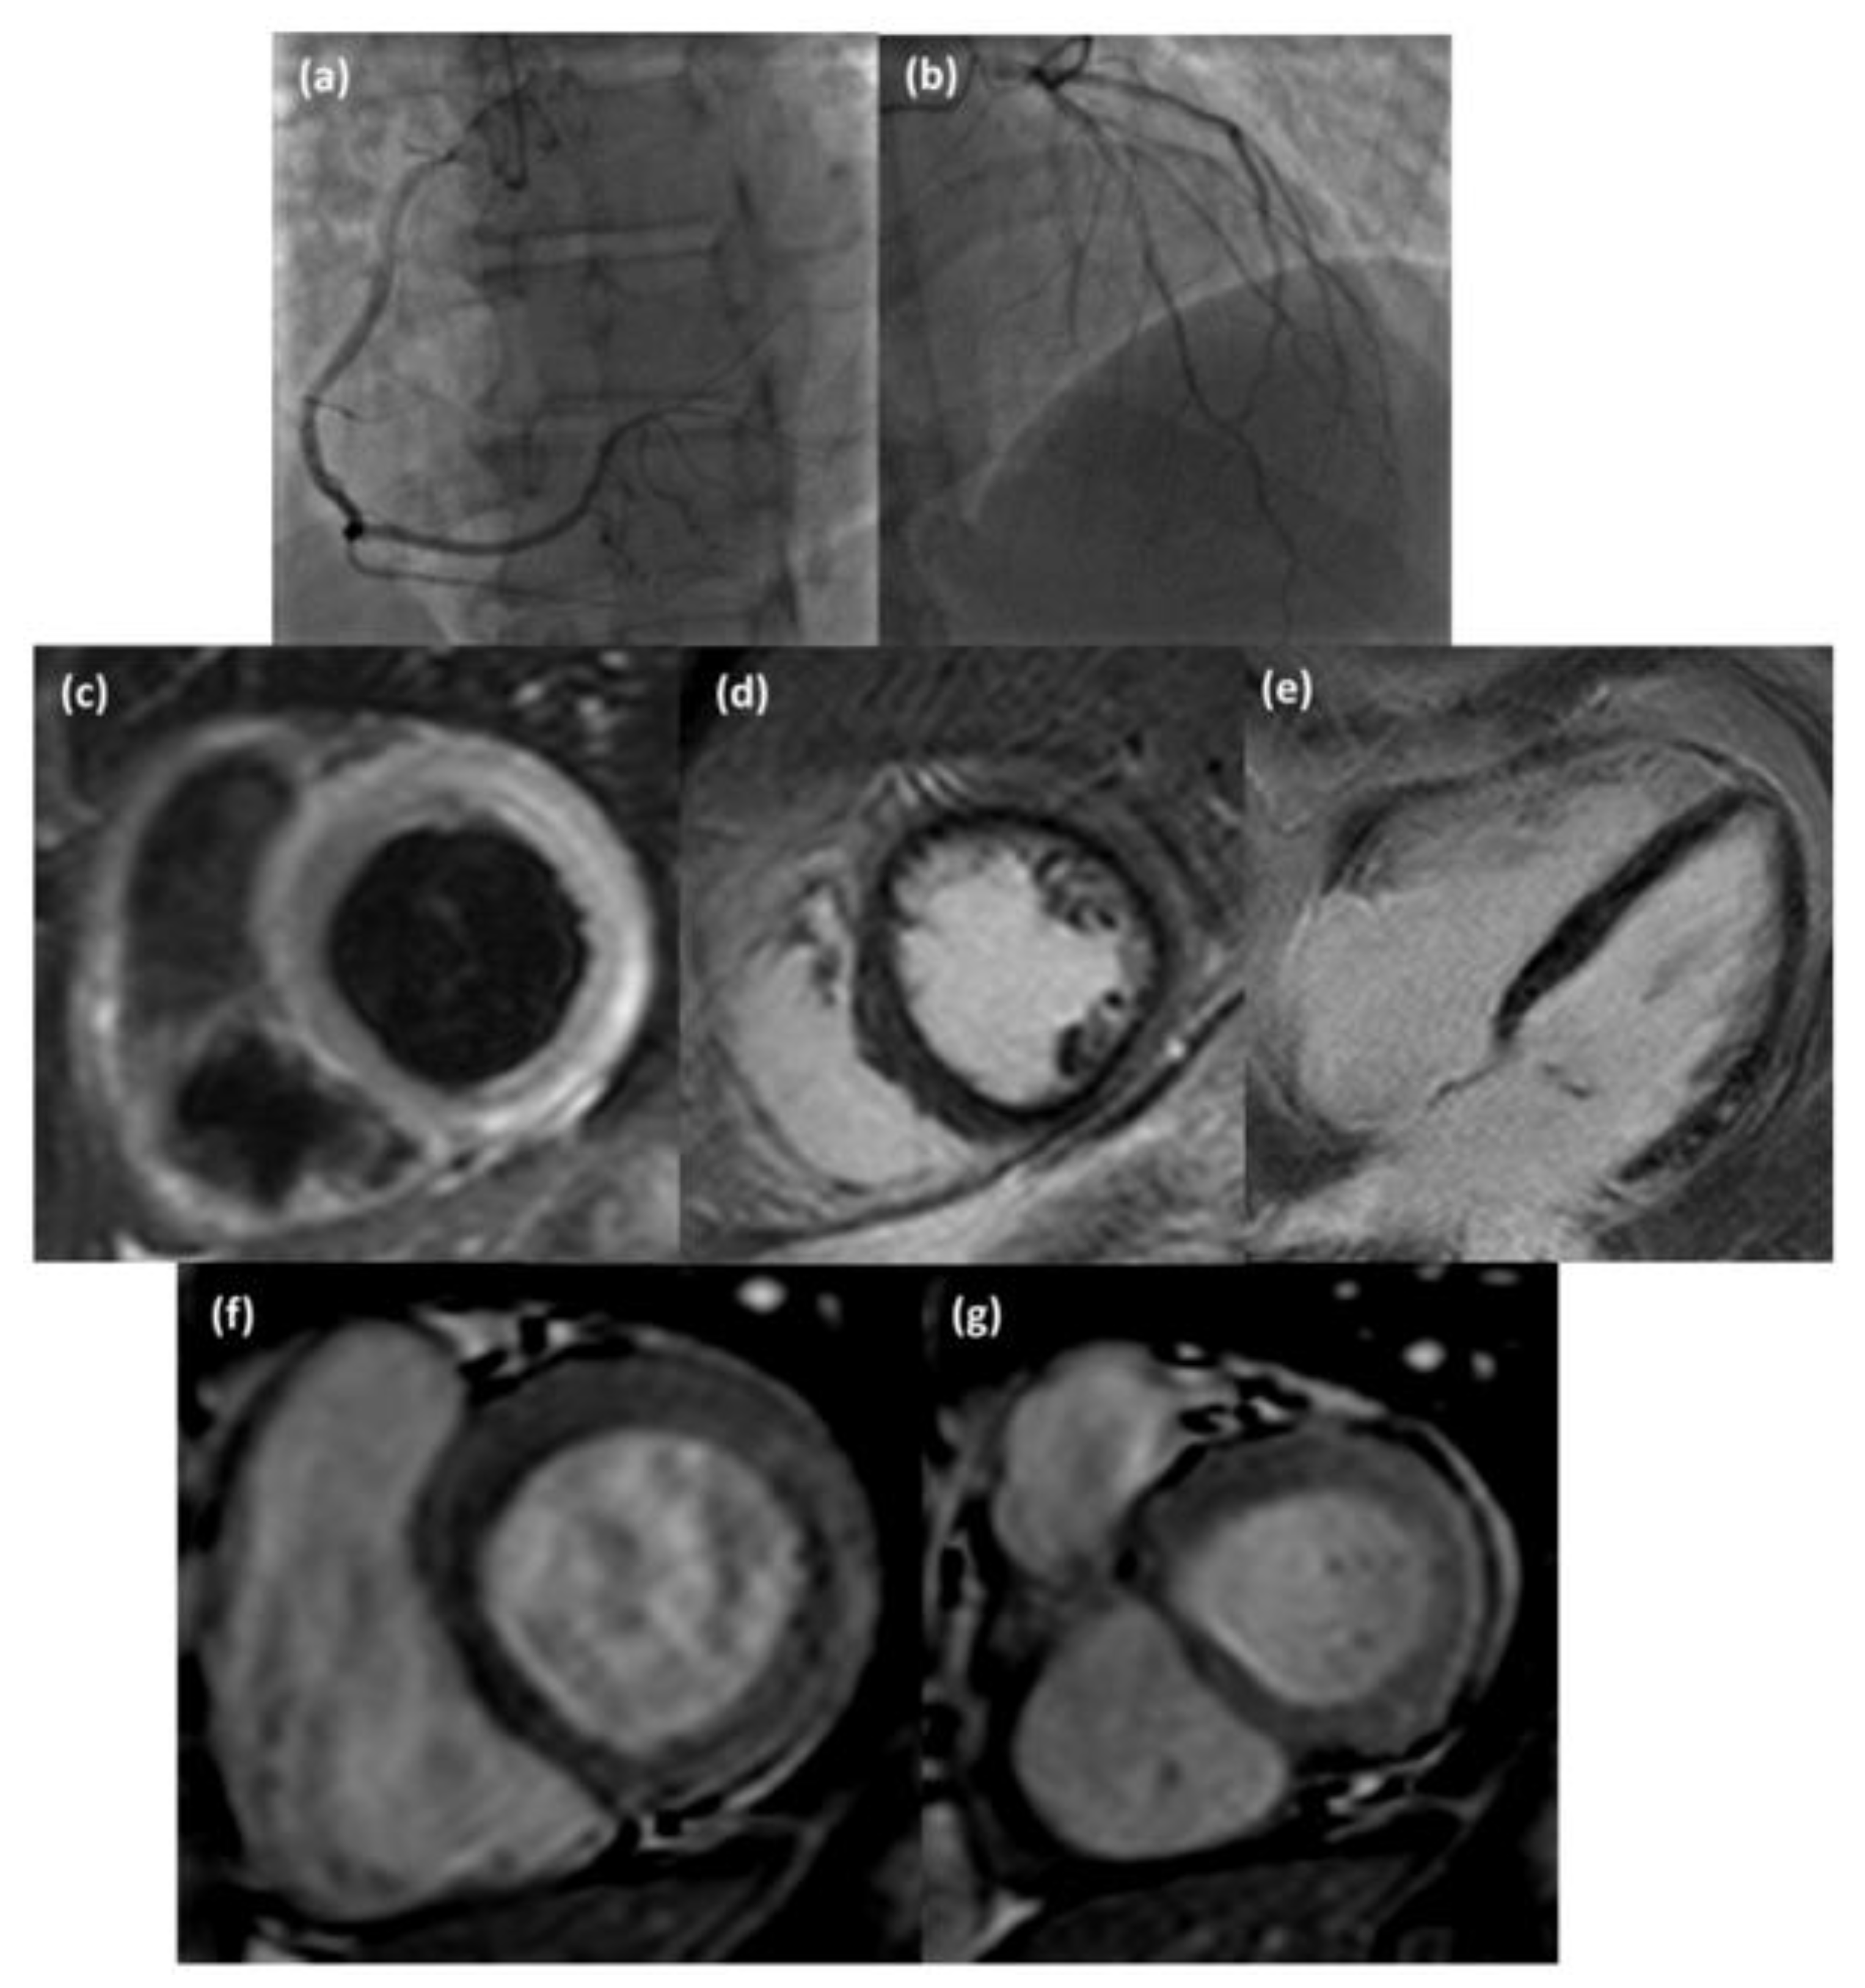

4.1. “Infarct-like” Presentation